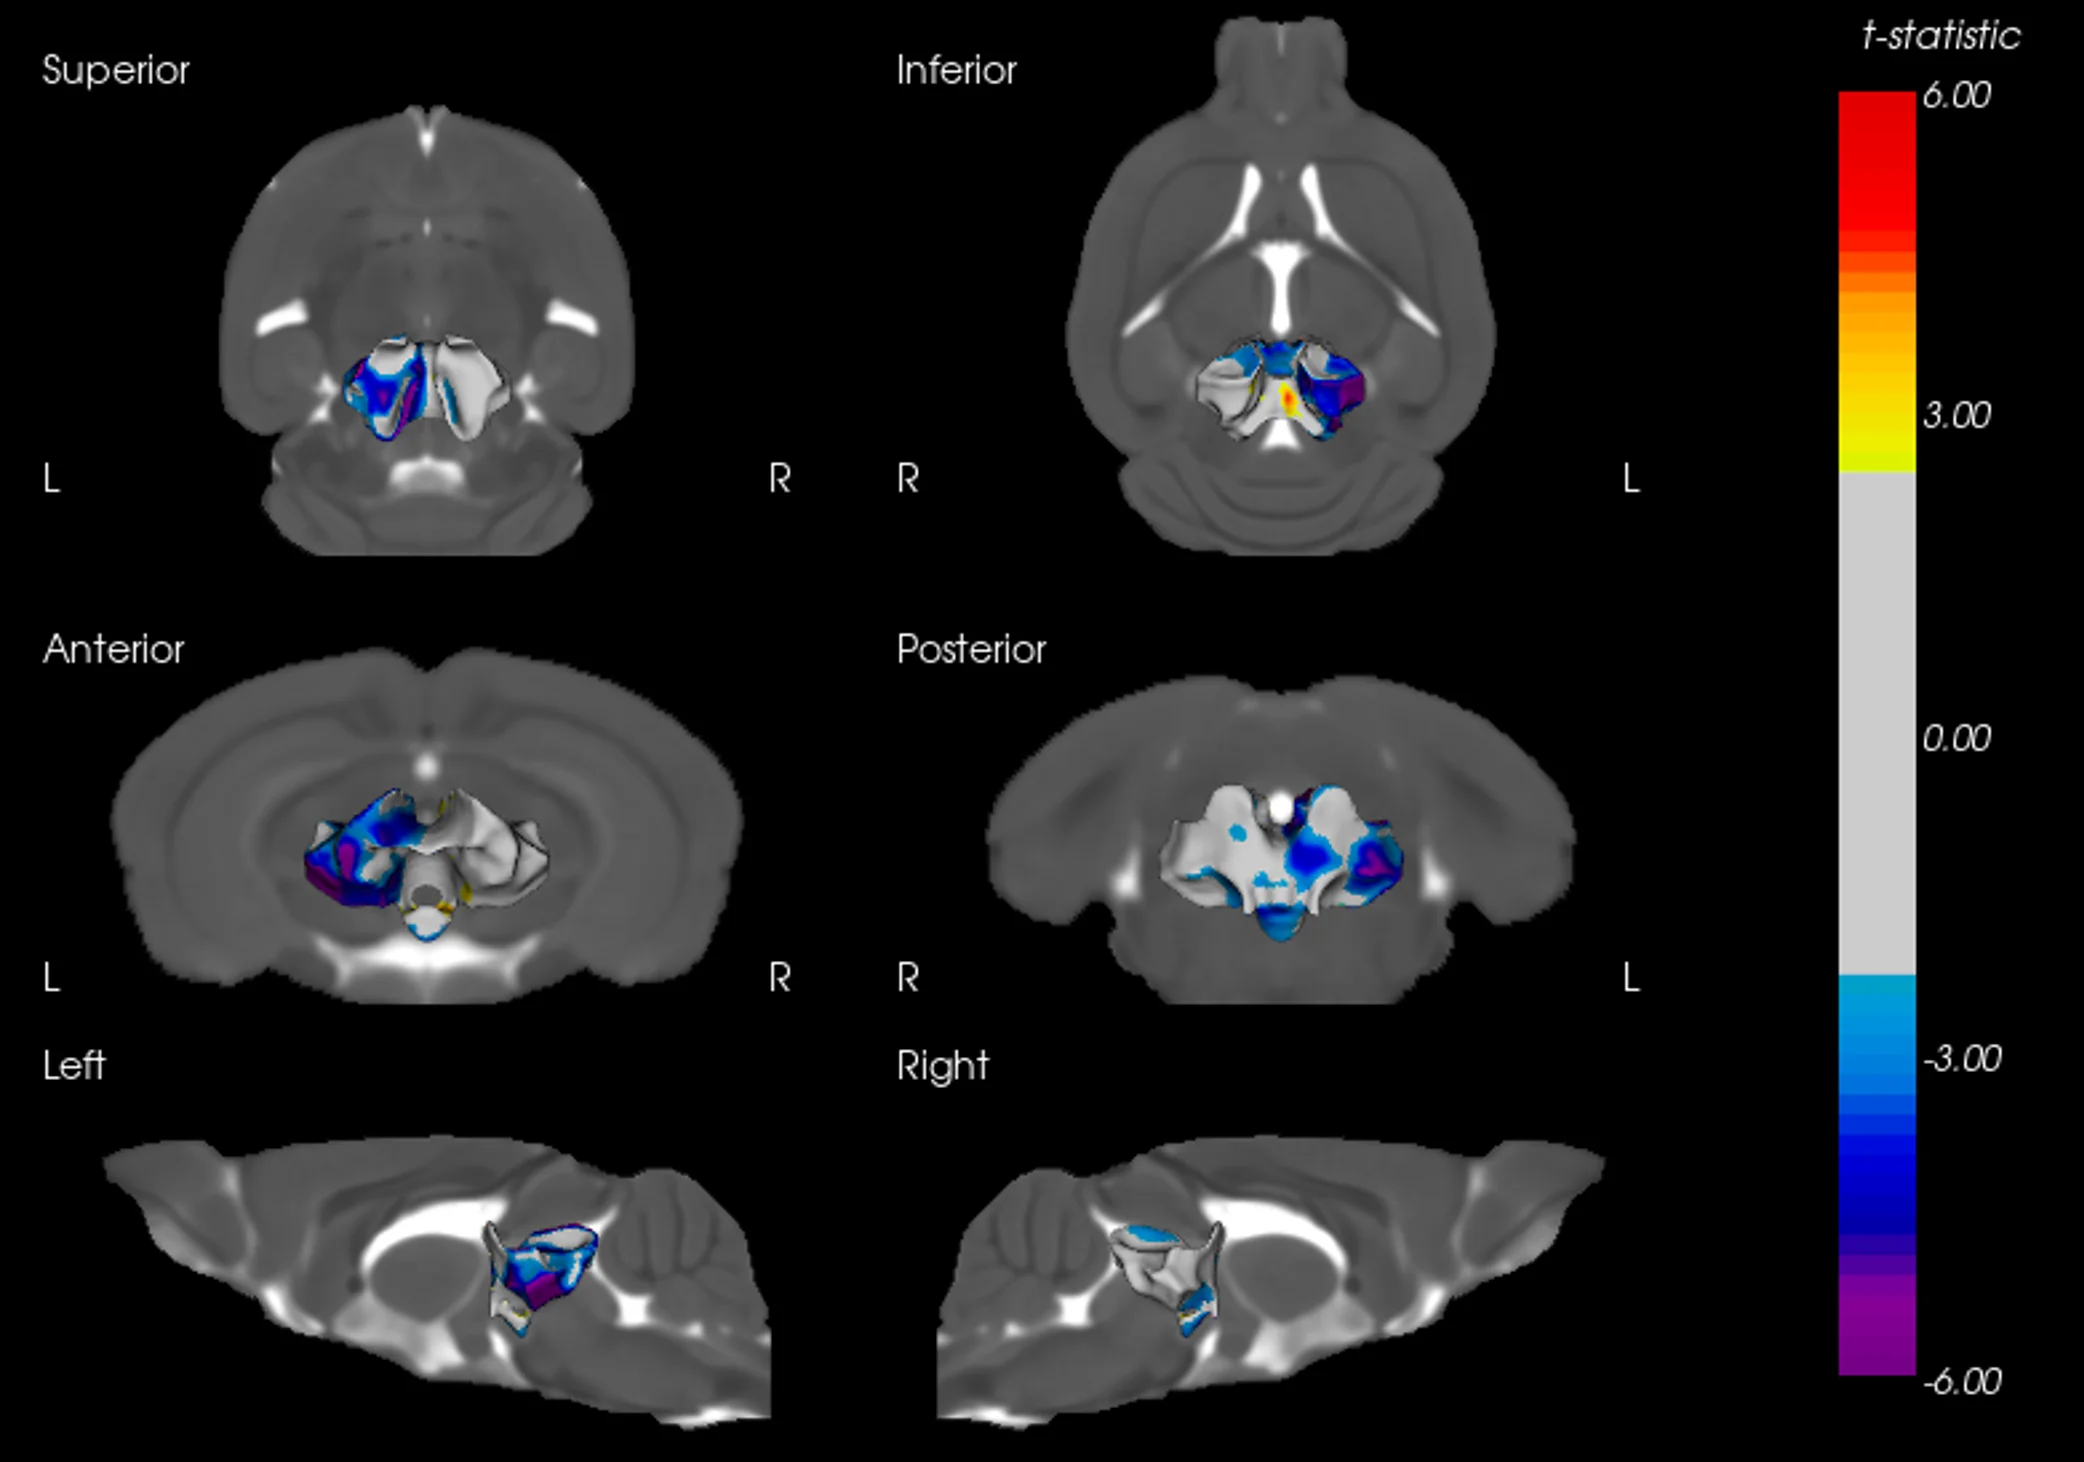

中脑萎缩模式

AAV-Tau 注射小鼠的中脑表面变形图。冷色表示具有显著负t统计量的区域,反映了左半球局部的表面向内位移(萎缩)。与年龄较大的小鼠相比,在年龄较小的小鼠中观察到了更广泛的空间变形模式。